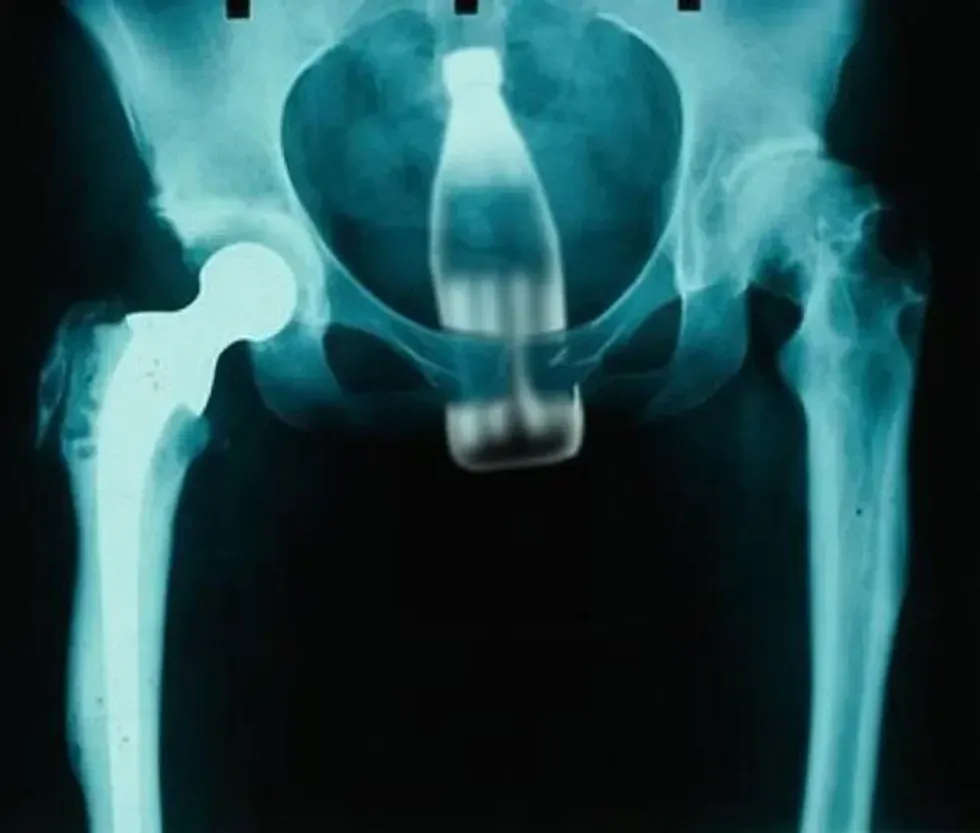

17. A Coke bottle